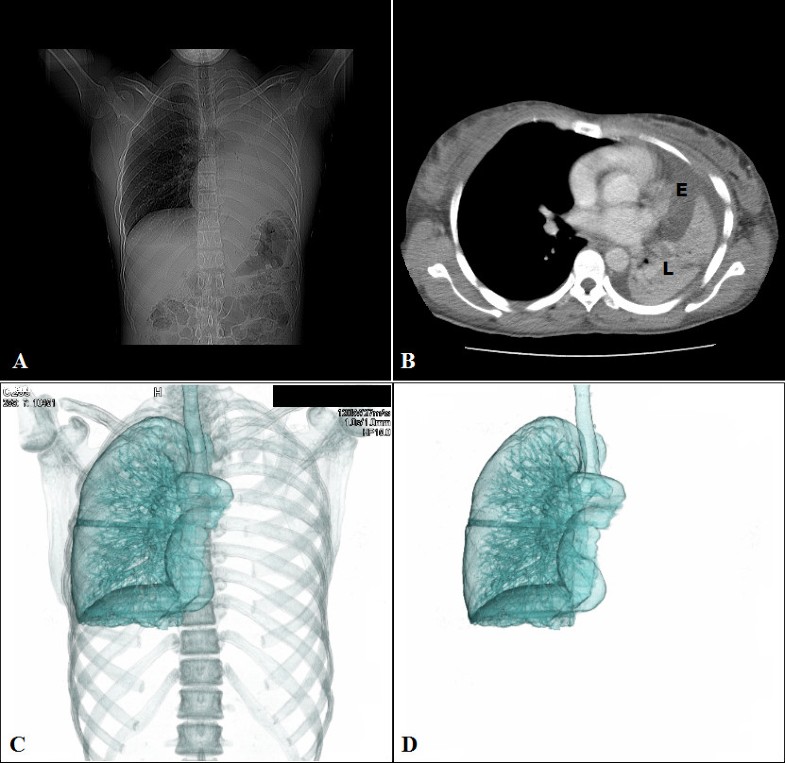

From www.cureus.com

Cureus Disseminated Gestational Trophoblastic Disease and Diffuse Alveolar Hemorrhage Treated Chest X Ray Molar Pregnancy if a molar pregnancy is diagnosed, the next step is typically a ct scan and pet scan to stage the disease. a health care provider who suspects a molar pregnancy is likely to order blood tests and an ultrasound. a molar pregnancy occurs when an egg and sperm join incorrectly at fertilization and create a noncancerous. There. Chest X Ray Molar Pregnancy.